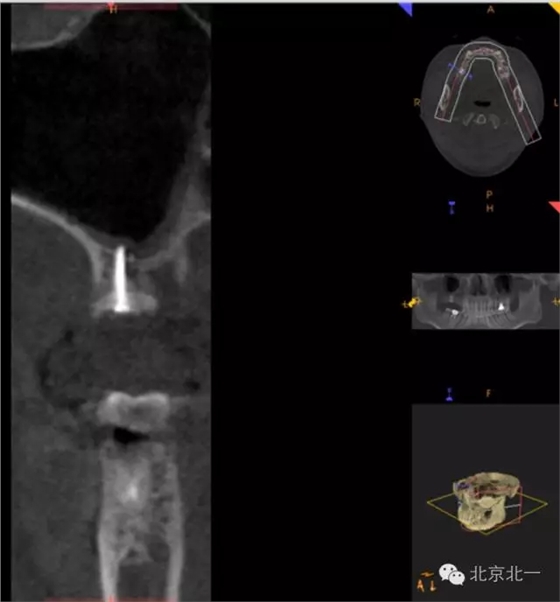

CBCT顯示,骨寬度可,骨高度不足,月3mm。頜間距離增大。

圖十八:手術(shù)前CBCT

圖十九:手術(shù)后當天CBCT

圖二十-二十二:ONLAY植骨半年后